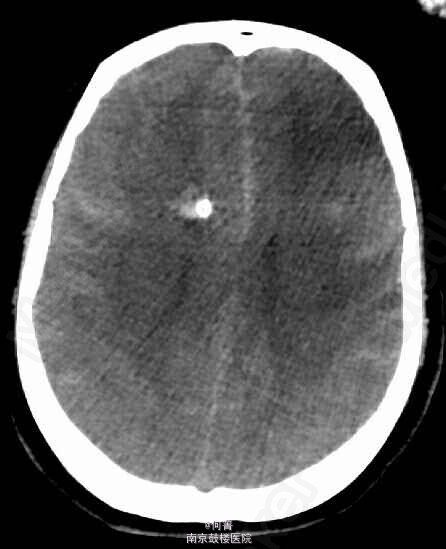

查体:BP:158/103mmHg,余生命体征平稳。专科查体:嗜睡状,呼之能应,查体欠合作;右侧额部留置有脑室外引流管,引出淡红色脑脊液;颈项强直。 辅助检查:CTA:蛛网膜下腔出血,脑室积血,右侧额叶血肿伴灶周水肿,脑实质明显肿胀,中线局部左移,右侧脑室见引流管。基底动脉瘤,其内密度不均匀,可疑血栓形成,大小约1.0x1.5cm;左侧椎动脉颅内段动脉瘤,大小约0.6x0.5cm;左侧大脑中动脉M1及M2D段交界区动脉瘤,截面大小约0.6*0.6厘米;右侧颈内动脉终段、左侧大脑中动脉M1段及椎动脉管腔不均匀,局部增粗,管壁欠光整。

诊断:1、蛛网膜下腔出血,2、颅内多发动脉瘤,3、高血压病 3级 极高危。治疗:予以抗血管痉挛、抑酸护胃、纠正低钾及对症治疗,行DSA检查,示基底动脉梭形动脉瘤;左侧小脑后下动脉起始部动脉瘤;左侧大脑中动脉分叉部膨大。行介入下动脉瘤夹闭术。